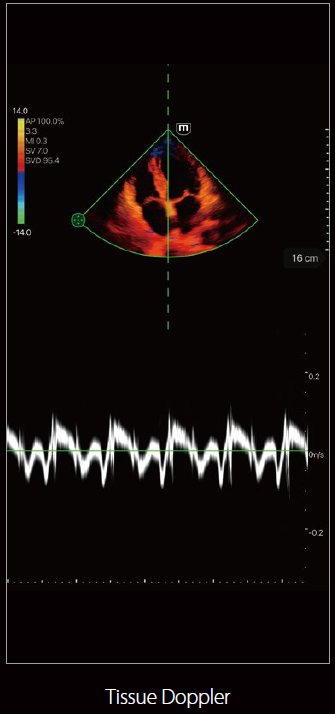

TE Air

صور متعلقة